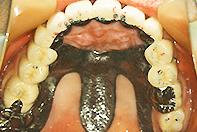

下顎Co-CrZL

アタッチメント